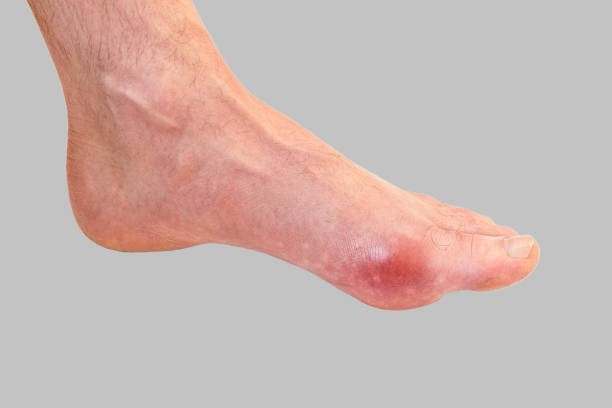

통풍증상 4. 급성 통풍 발작

통풍 증상 네 번째는 급성 통풍 발작인데 엄지발가락, 발목 등 한 곳의 관절이 갑자기 빨갛게 부어오르고 손댈 수 없을 정도로 통증이 심한데 발뒤꿈치, 팔목, 손가락, 귀 등에서 나타나며 급성 통풍성 관절염이라고 부르기도 합니다.